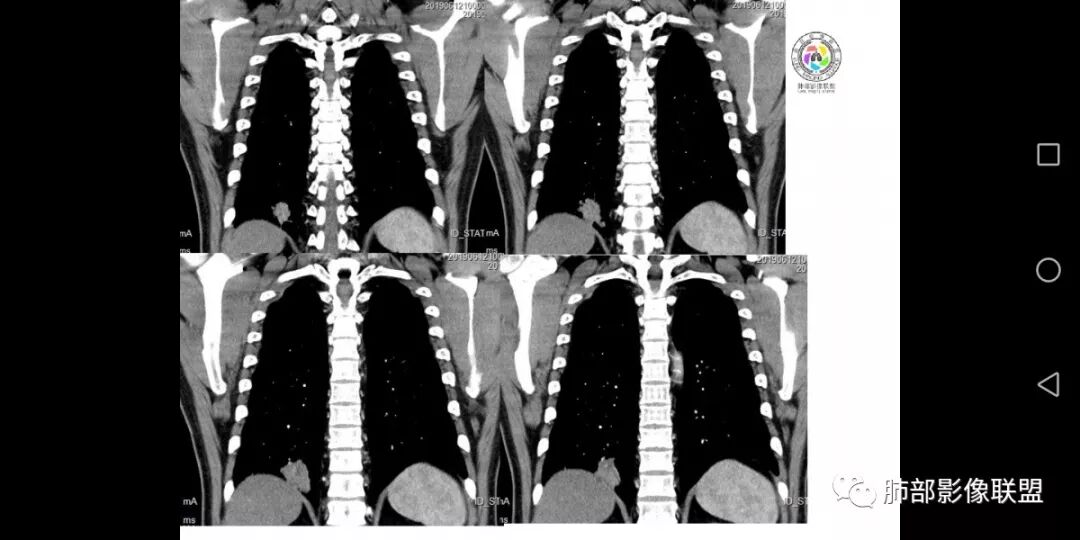

患者男,45岁,因乏力、低热、心悸入院,最高体温38℃,偶有咳嗽、无咳痰、咯血,肿瘤标志物阴性。

影像资料

增强特点:多为明显强化,CT值增加40-80HU之间),一般很少出现深分叶、钙化及淋巴结肿大的特点,常可与周围性肺癌鉴别。

1.多位于肺表浅部位,近胸膜或叶间裂。

2.单发病灶多见,结节影或块影呈类圆形或椭圆形,直径多为1-6cm。

3.部分可见支气管管像,但很少支气管截断。

4.边缘可清楚或模糊,可有浅分叶、长毛刺或棘状突起,部分病灶周边磨玻璃影。有时可见“桃尖征”、“平直征”或“刀切征”等良性征象。

5.病灶密度均匀,偶见空洞及钙化。强化较明显且持续,均匀或不均匀。